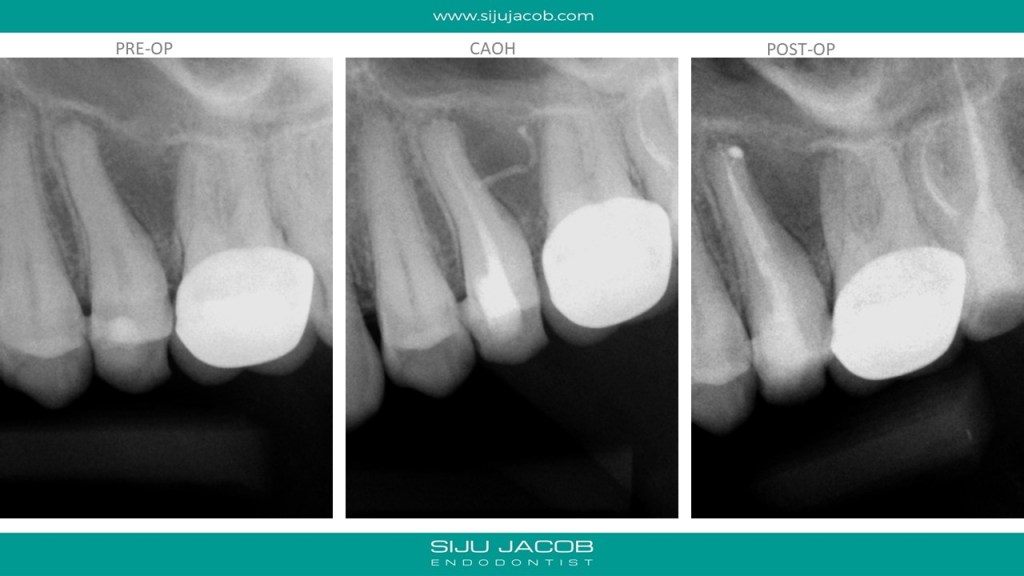

This patient presented with a lesion in between the second pre-molar and first molar. The second pre-molar tested non-vital. In the caoh radiograph taken after the first session, You can see the calcium hydroxide going through a lateral canal into the lateral lesion. I however, couldn’t get sealer into the the lateral canal during the obturation. It still healed pretty well though.